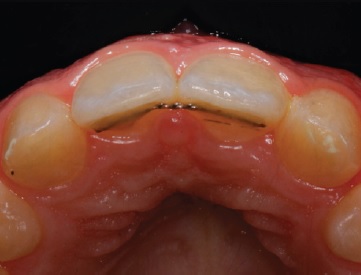

Orthodontic treatment involving space closure was performed. After golden proportion (Figure 4) and Bolton’s anterior analysis, the presence of a 77.7% dental discrepancy in the anterior relation with mandibular excess was confirmed (14, 13, 11, 21, 23, 24, / 33, 32, 31, 41, 42, 43). Due to the agenesis of the maxillary lateral incisors and the need to perform esthetic restorations in the upper arch to improve smile harmony, a similar Bolton anterior discrepancy of 76% was obtained after restorations. After orthodontic treatment, shade selection was accomplished using a Vita Shade Guide (Figure 5), and dental bleaching was performed. Afterward, according to clinical findings and with careful consideration of all treatment options available for rehabilitation, it was decided that the maxillary canines and first premolars would be additively remodeled to the shape of lateral incisors and canines, respectively, using direct composite (Figure 6), which provides advantages in symmetrical cases.

Figure 6 Case 1: Maxillary canines and first premolars additively remodeled to the shape of lateral incisors and canines, respectively, using direct composite ((A) right, (B) frontal, and (C) left aspects).

Because the patient had a diastema, the risk of treatment relapse was overcome with long-term fixed retention using a bonded retainer (Figure 7).16 Meanwhile, the material used for the build-up was a hybrid composite (BRILLIANT EverGlow®, Coltène-Whaledent, Altstätten, Switzerland). Lastly, occlusal adjustments were performed, and final extra-oral photos (Figure 8) revealed a satisfactory integration of the restorations.